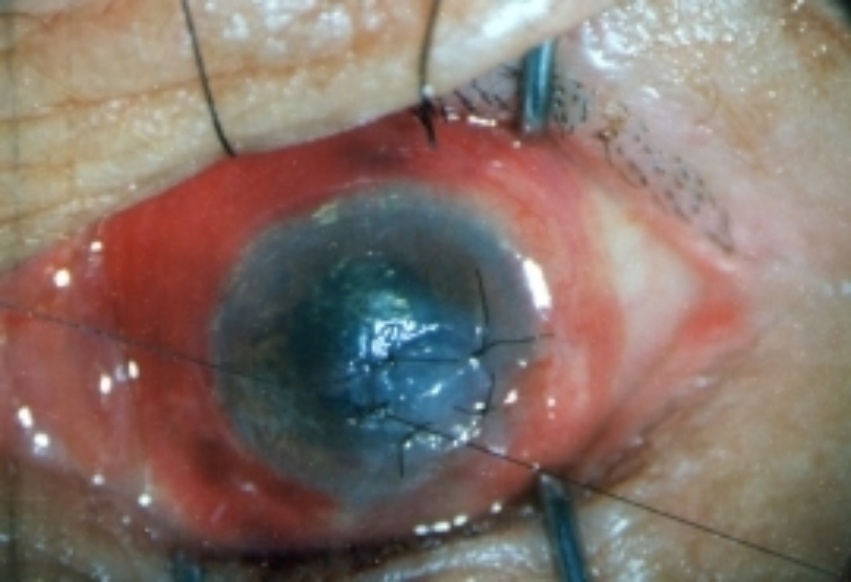

移植片的转归;10例中,术后1个月~1年植片透明愈合1例,半透明4例,混浊3例,植片脱落2例。随访5~8年植片半透明4例,混浊6例(其中植片有新生血管2例,脱落2例包括在内)。视力:10例中,出院时视力较术前提高3行以上或从眼前手动、指数提高到0.1以上者3例,无变化7例;随访4个月~8年视力提高3行以上或从眼前手动、指数提高到0.1以上者3例,无变化6例,有1例植片由透明变成混浊,视力由出院时0.5下降到眼前手动(见附录部分病例彩色图片)。

附 录

鹅角膜板层移植部分病例